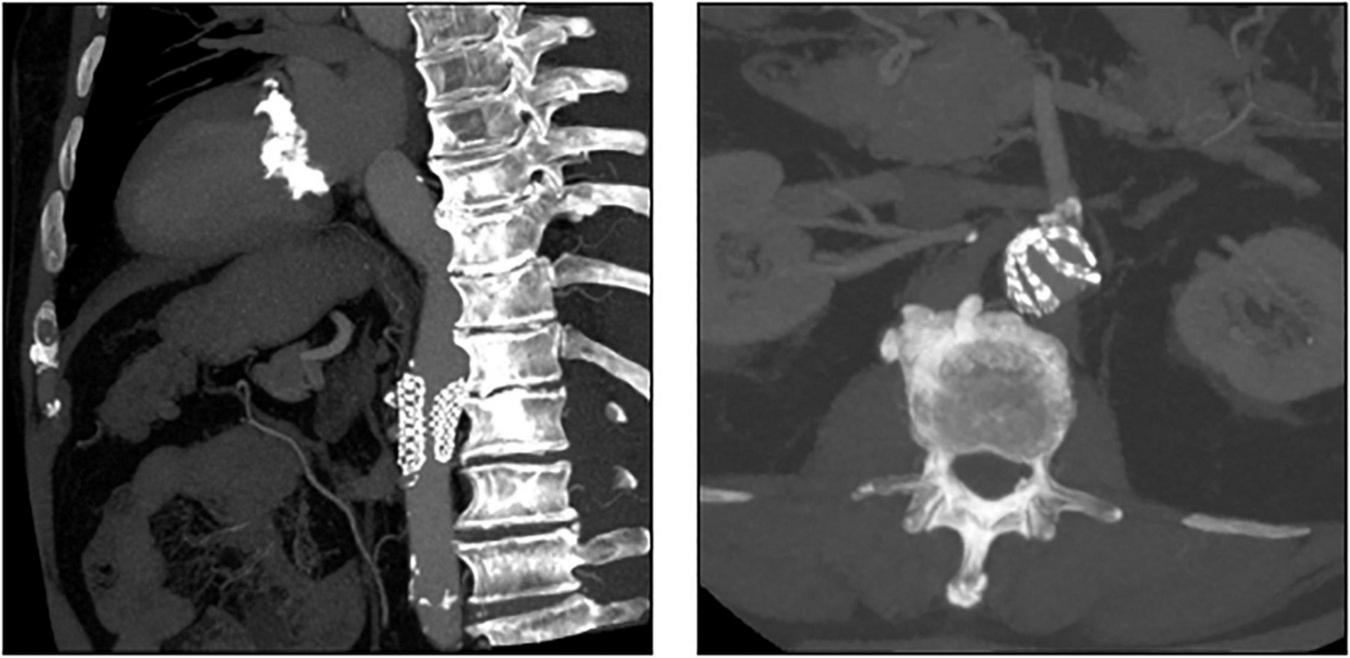

CT exams were performed on average 26.3 months after TAVI (range 2–84 months). Similar to the overall distribution in all TVEM patients (Figure 1B), the embolized valve was left in the aortic root or the ascending aorta in eight of the examined patients. Hypoattenuated leaflet thickening (HALT) was detected in two embolized valves (Figure 2). In these two patients stent frames showed no deformation. In addition, parts of the stent frame protruding into the aortic wall, yet without signs of dissection, were observed in three patients (Figure 3).

FIGURE 3

Protruding stent frames into the aortic wall. CT follow-up images from patients 3, 4, and 6 (Table 5) revealed parts of the upper crown of the stent frame protruding into the aortic wall.

Subclinical leaflet thrombosis characterized by hypoattenuated leaflet thickening (HALT) is a frequent finding in transcatheter bioprosthetic aortic valves with a prevalence of up to 28% in short- and long-term CT follow-up (4, 5, 14). To our knowledge, our study is the first to systematically examine embolized valves by CT after mid- to long-term follow-up. HALT was detected in the embolized valves in two TVEM patients (Figure 2). Since the number of patients in our imaging sub-study is low it is not possible to draw definite conclusions. Of note, both patients with HALT did not take oral anticoagulants which have been shown to prevent the formation of leaflet thrombosis. In addition, our findings advise some caution as parts of the upper crown of embolized self-expanding valves protruding into the aortic wall were observed in three patients (Figure 3). This is reminiscent of another case from our TVEM cohort complicated by valve embolization due to pop-up of a 25 mm Portico self-expanding valve. The embolized valve was snared and pulled into the ascending aorta to avoid coronary obstruction. After successful implantation of a second transcatheter valve (23 mm Edwards Sapien 3) the patient developed hemorrhagic shock. Angiography revealed perforation of the ascending aorta by a part of the upper crown of the THV protruding through the aortic wall. The valve was surgically removed, and the ascending aorta repaired on cardiopulmonary bypass (Figure 6). Accordingly, interventionalists should be aware of this potential complication when embolized valves have to be actively pulled up into the ascending aorta using a snare. Patients should be examined by CT in a timely fashion to rule out perforation of the ascending aorta if they develop hemodynamic instability in the postinterventional course.